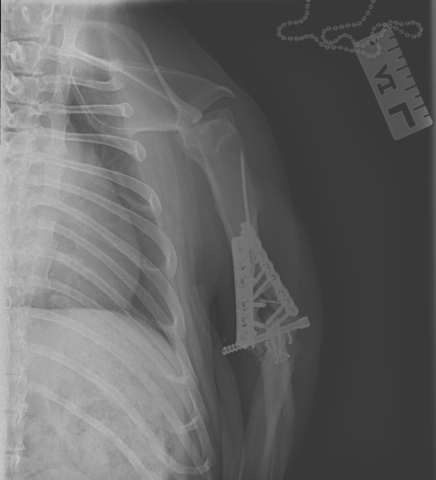

フレンチブルドッグ5歳13kgの左上腕骨Y字(関節内)骨折に対して、リハビリを行いました。

エックス線で骨癒合が確認出来ましたが、手根関節と肘関節の可動域の屈伸運動をご自宅でも行っていただき、順調に回復を目指します。